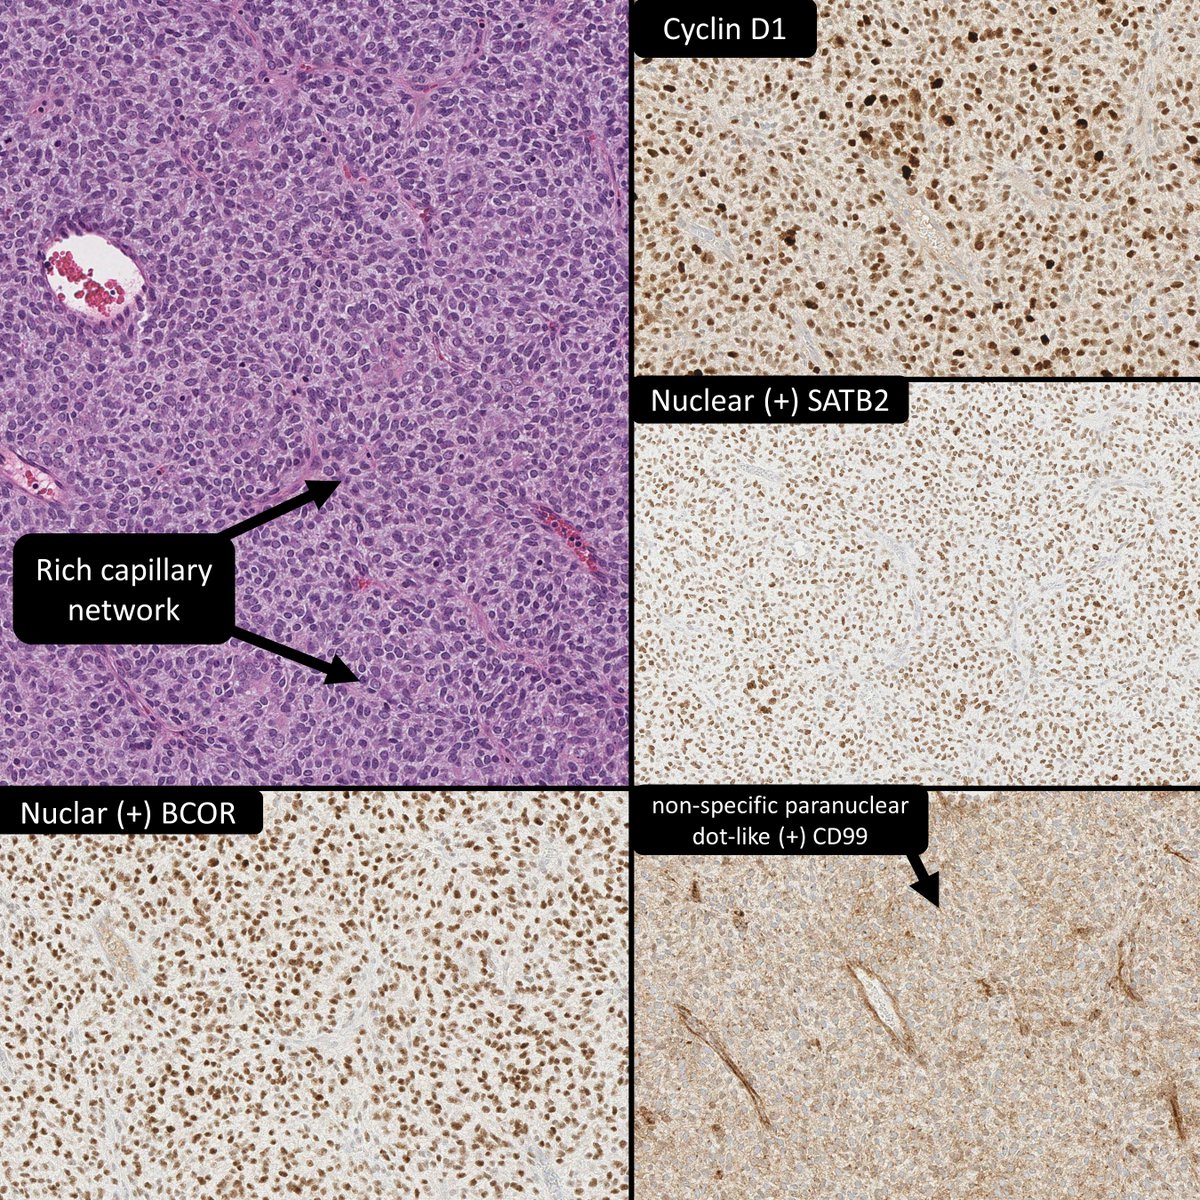

65 year old man posterior auricular neck deep dermal nodule. easy peezy?#dermpath #PathTwitter #dermatology Etan Marks, DO @ArjunRamaiya1 Lorand Kis Olaleke Folaranmi Tristan Rutland MBBS FRCPA IFCAP Trish Stratus Marcelasaeblima. Allison Osmond MD MSc FRCPC Ahmed Alomari, MD Gonzalo De Toro